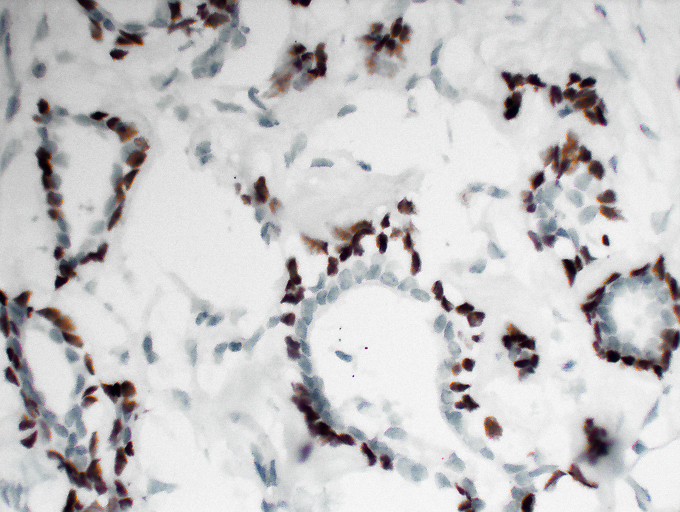

p63 (Phospho Ser395) Cell-Based Colorimetric ELISA Kit

ELISA

Colorimetric

p63 (Phospho Ser395) Rabbit pAb

YP0486

预览→